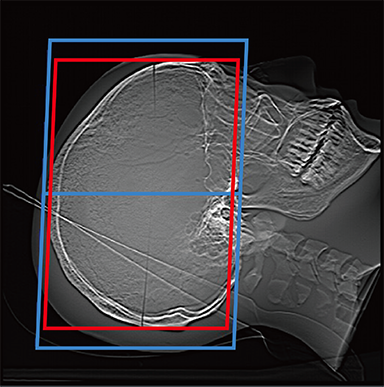

FCT iStream automatically*2 sets the scanning range using the scanogram image by AutoPose function. Since the margins can be set in advance, the range can be customized according to the preference of the facility. iTilt automatically creates and enables observation of tilted images during scanning.

When set to OM Line

When set to SM Line

When set to RB Line

Red: automatically set position, Blue: automatically set position + margin setting position